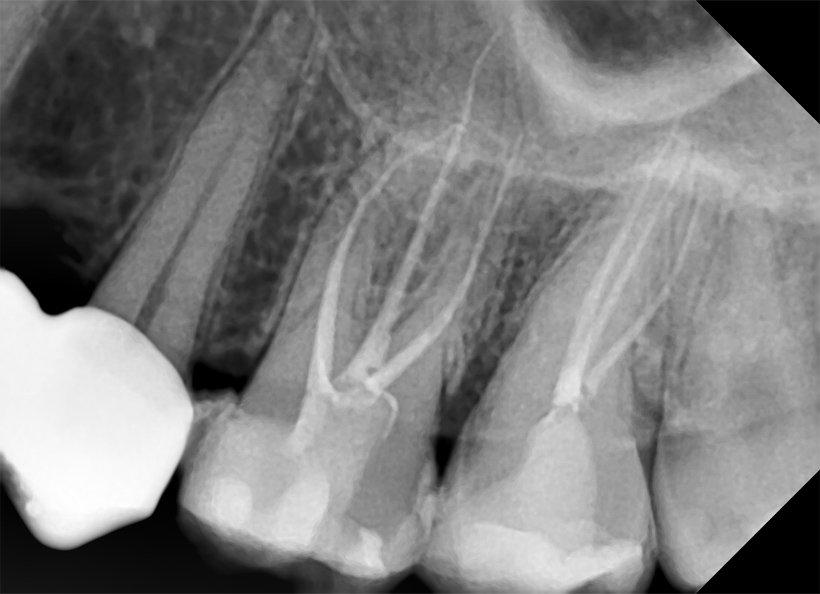

Radiografia digitală ocluzală